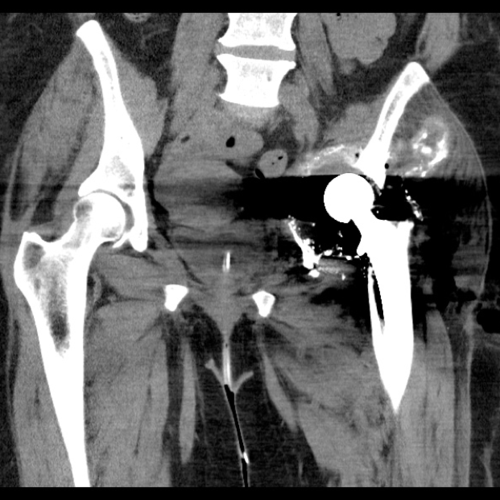

CT scan showing the patient’s pelvis without the acetabular metal work. This was used to make the hemipelvic 3D model seen below.

CT scan demonstrates optimal positioning of the acetabular component

CT scan at 7-months shows no migration of the implant.